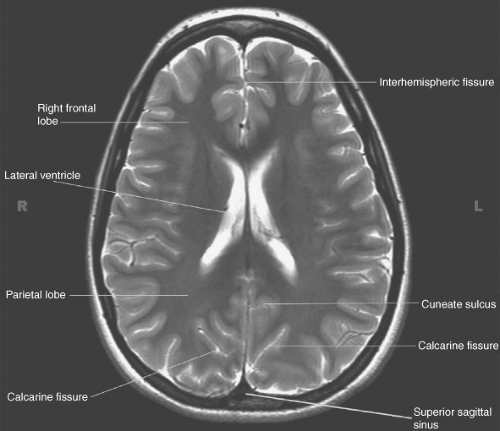

what type of plane is this

axial plane

MRI

Uses magnetic fields, radio waves and computerised enhancement to map out brain structure

Detailed images of various structures, e.g. soft tissue, nerve vessels

Can spot subtle issues

Can spot different pathologies to CT scans and X-rays